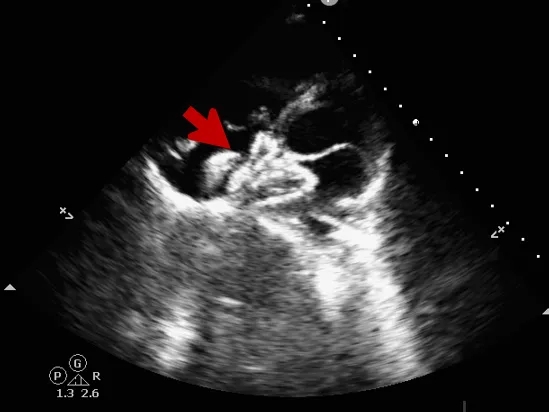

术中复测

超声可见房间隔连续中断,彩色多普勒可见过隔血流

测量房间隔缺损直径最大为23.9mm,房间隔总长53.8mm